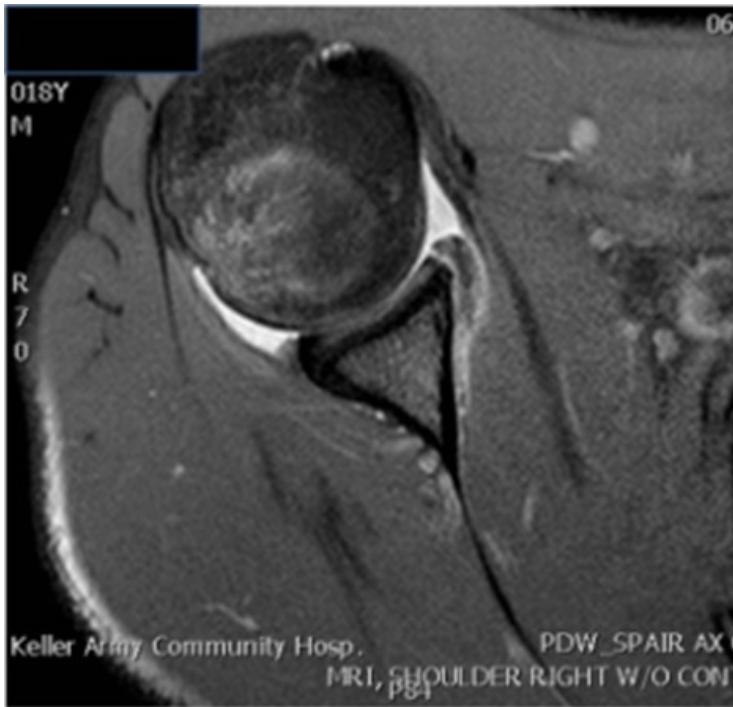

Imaging

Questions for analysis:

- What are the two findings in recurrent shoulder dislocation?

- What do you see on the images?

Case Study 4: Recurrent Shoulder Instability

A 35-year-old male presented in clinic complaining of left shoulder pain and instability.

History

- Recurrent dislocation history

- Previous treatments: Multiple reductions and physiotherapy

- Treatment failure: Physiotherapy was ineffective

Examination

- Symmetrical shoulders on inspection

- Range of motion: Good and pain-free

- Apprehension test: Positive ✅ (indicates instability)